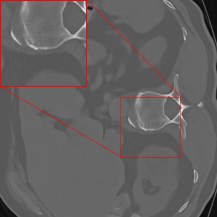

Figure 3 shows reconstruction results from the three networks for a test sample from the LoDoPaB-CT test dataset and one from the 2016LDCTGC dataset. All trained networks successfully improve the FBP reconstructions, as shown by the improved image quality and finer structural details.

Figure 3: Reconstruction results for two test samples from the LoDoPaB-CT test dataset (top row) and the 2016LDCTGC dataset (bottom row). The first column displays the ground truth, followed by the FBP in the second column. The next three columns present reconstructions by the Gaussian denoisers DRUNet, KBNet, and Restormer. Each pretrained denoiser model was trained for 96 epochs on 1791 image pairs from either the LoDoPaB-CT training dataset or the 2016LDCTGC dataset. The proposed two-stage method effectively enhances the FBP reconstructions in each case, as demonstrated by the PSNR and SSIM metrics provided below each subimage.